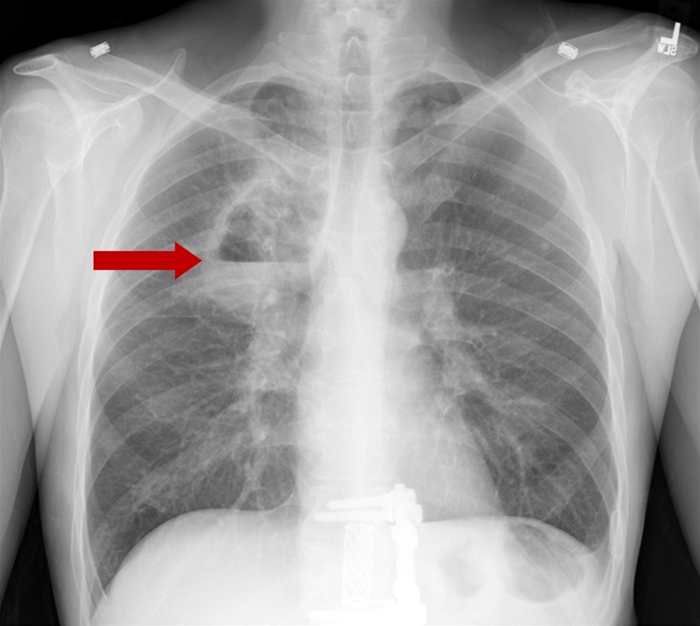

Secondary Pneumonia

Secondary bacterial pneumonia is the most common complication of influenza but is rare in young individuals (most are age >65). An exception occurs with community-associated methicillin-resistant Staphylococcus aureus (CA-MRSA), an organism that preferentially attacks young patients with influenza. CA-MRSA causes severe, necrotizing pneumonia that is rapidly progressive and often fatal. Manifestations include high fever, productive cough with hemoptysis, leukopenia, and multilobar cavitary infiltrates. Most patients require admission to the intensive care unit and broad-spectrum, empiric antibiotics, including either vancomycin or linezolid.